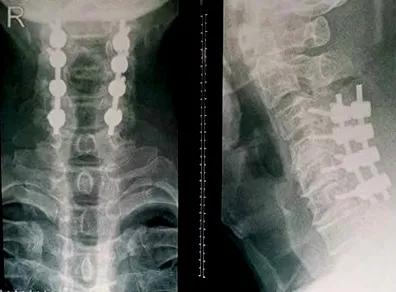

患者是一名年轻男性,一年多来,常伴有左上肢麻木不适,就在一个月前,患者在进行理疗治疗时症状加重,出现头部不能屈曲及过伸,左上肢麻木明显,夜不能眠,令他痛苦不堪。入住我院龙湾院区脊柱关节外科后,经检查发现颈椎间盘突出,神经根受压明显。

经过脊柱关节外科中心会诊,诊断患者为神经根型颈椎病,根据患者的典型症状,医生建议行微创颈椎后路椎间孔切开术KEY-hole(钥匙孔技术)。在脊柱关节外科中心手术团队的共同努力下,手术过程顺利,术后患者恢复良好。